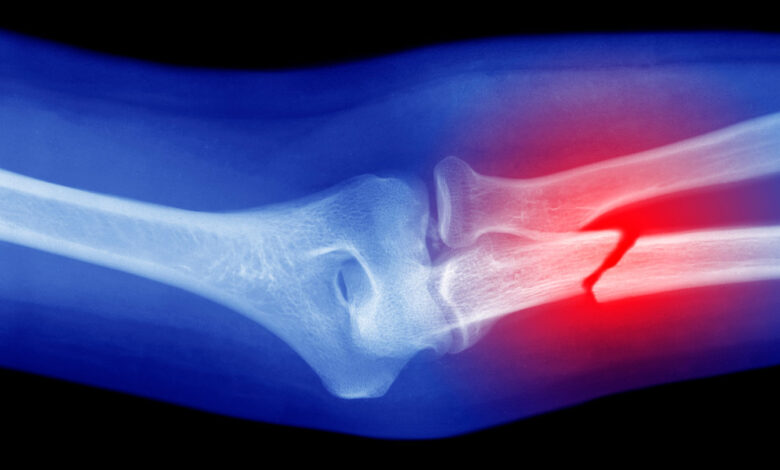

zlomenina: (podstatné jméno) Přestávka. (sloveso) Rozbít něco a způsobit praskliny nebo rozdělení něčeho.